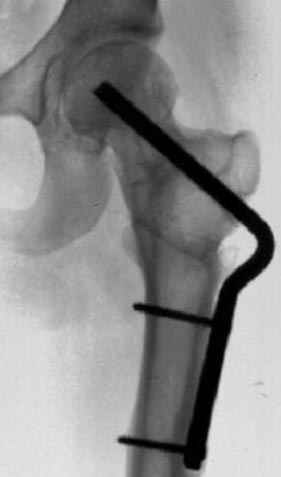

Несколько снимков из моей коллекции, чтобы разьяснить, почему мы до сих пор делаем различные варианты остеотомии.

На рисунке N1 предоперационный план лечения ложного сустава шейки бедра- линия ложного сустава, угол и направление введения импланта, клиновидная остеотомия в градусах и миллиметрах, второй снимок после коррекции, расчет, на сколько удлиняется конечность и размеры импланта;

N3 рисунок окончательный снимок, после операции моя рентгенограмма должен выглядеть примерно как эта картина. На N4 снимке клин перед удалением; N5 послеоперации 3 нед.; N6 окончательная рентгенограмма.

(доложен в Ст. Петербурге 2003 и в Москве 2004)

варус при проксимальном отделе 95 градусной пластиной.

пластическая модель; и коррекция бедра аппаратом Илизарова.